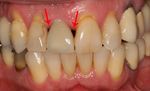

Peri-implantitis

Bone loss (peri-implantitis) on implants over 7 years in a heavy smoker

Black triangles

Black triangles caused by bone loss between implants and natural teeth